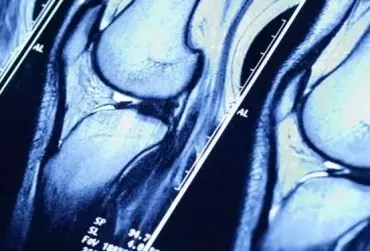

Choroba zwyrodnieniowa stawów to najczęstsza choroba układu ruchu. Nierzadko gabinety fizjoterapeutów odwiedzają pacjenci cierpiący na osteoartrozę, pragnąc poprzez terapię spowolnić lub zahamować rozwój choroby. Jednym z ważnych elementów całego procesu leczenia, zwalczającym chorobę zwyrodnieniową stawów, jest aktywność fizyczna. Niestety, często pacjenci nie potrafią zmotywować się do ruchu ze względu na przyzwyczajenie do siedzącego trybu życia lub zbyt dużą masę ciała. Jak rozwiązać ten problem i pomóc im znaleźć motywację do ćwiczeń? Jak wspierać walkę z otyłością i nadwagą u pacjentów z osteoartrozą?

Wiosna to początek sezonu sportowego i... początek możliwych problemów ze stawami. Aktywny tryb życia staje się w naszym społeczeństwie coraz popularniejszy, nie tylko wśród młodych osób. Uprawianie sportu jest modne. Dzięki dużej dostępności do boisk, siłowni, kortów, ścieżek rowerowych i tras dla biegaczy w dużych miastach aktywność sportowa możliwa jest na wyciągnięcie ręki.

Nierzadko możemy spotkać się ze stwierdzeniem, że regularne uprawianie sportu stanowi formę działania profilaktycznego: może pomóc uchronić nas przed różnymi schorzeniami. Aktywnie trenując, pragniemy jak najlepiej zadbać o swoje zdrowie i samopoczucie. Jednak nie zawsze zdajemy sobie sprawę, że czasem to właśnie uprawianie sportu bywa przyczyną różnych dolegliwości. Tak może się stać na przykład w przypadku rozwoju ChZS. Co kryje się pod tym tajemniczo brzmiącym skrótem? I czy faktycznie jako sportowcy mamy się czego obawiać?